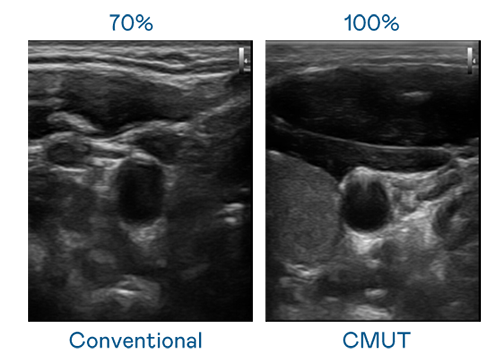

CMUT 技術是一種用電容式微機電元件來產生超音波訊號的技術。與傳統 PZT 壓電式技術相比,CMUT 頻寬增加 30%,更寬頻的超音波訊號讓影像解析度大幅提升,是實現高影像品質醫療超音波掃描、促進精準醫療發展的關鍵技術。

大頻寬帶來超清晰影像

超音波影像的解析度高低,首先取決於探頭能發出的訊號頻寬。918博天堂 CMUT 可提供高清晰的超音波訊號,提供高頻寬、高靈敏度、影像紋理細節更高的超音波影像,協助醫護人員縮短影像判讀時間及利用精準的醫療影像進行診斷。